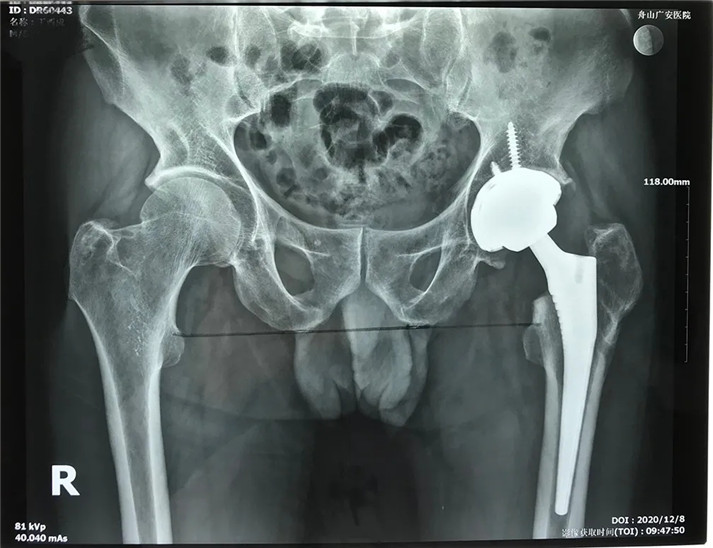

經(jīng)過周密的術前準備,在身體符合手術指征后,丁大哥接受了全髖關節(jié)置換術。術中發(fā)現(xiàn)術前規(guī)劃產(chǎn)生的假體大小、位置、角度均非常理想,大大縮短了手術時間,全程十分順利。術后,丁先生恢復良好,次日即可下床活動。目前術后一個月,可以干活了。對于此次手術,丁大哥及其家屬表示非常滿意。

術后